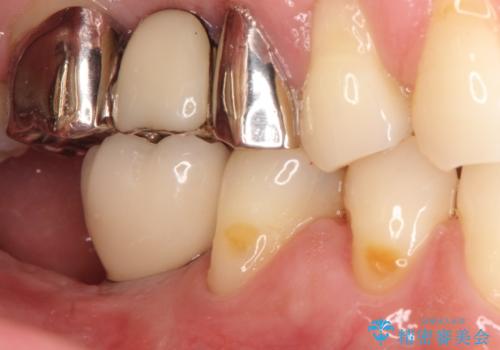

奥歯が痛い。抜歯~奥歯のインプラント

- 奥歯が破折していたため、抜歯を行ったあとインプラントを埋入して咬合回復を行っております。